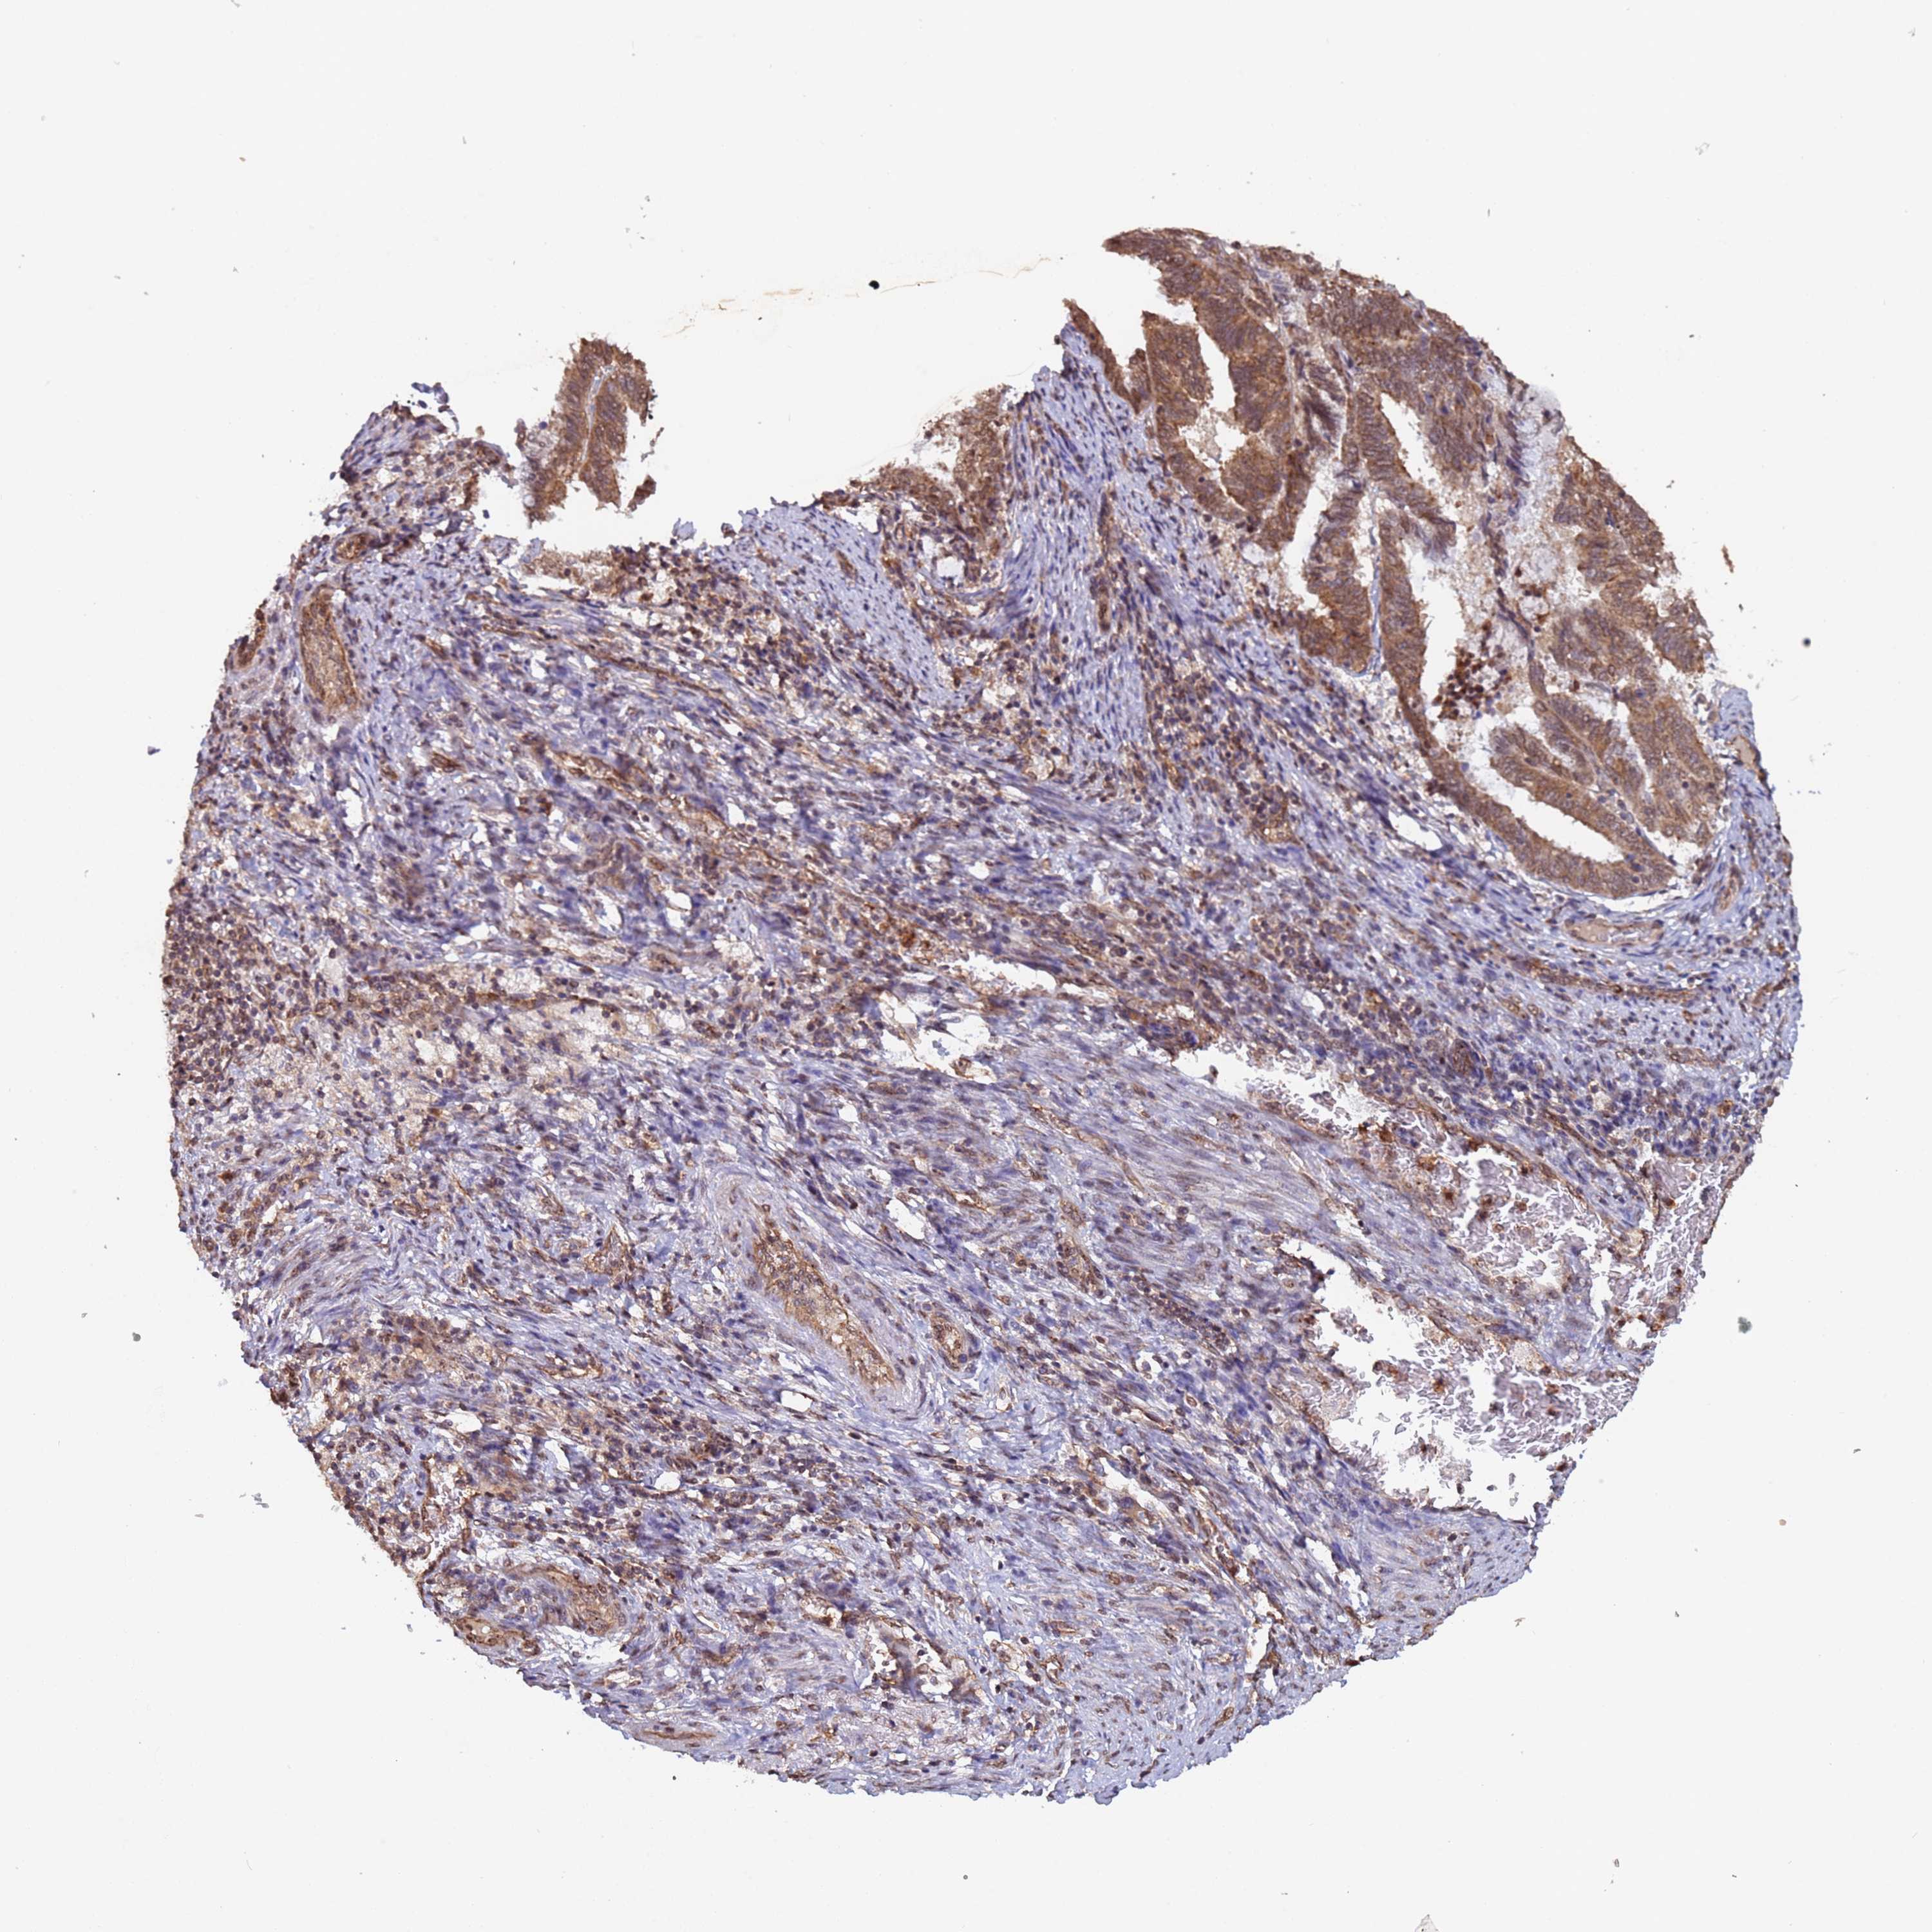

ENDOMETRIAL CANCER - Protein expressioni

A mouse-over function shows sample information and annotation data. Click on an image to view it in a full screen mode. Samples can be filtered based on level of antibody staining by selecting one or several of the following categories: high, medium, low and not detected. The assay and annotation is described here.

Note that samples used for immunohistochemistry by the Human Protein Atlas do not correspond to samples in the TCGA dataset.

Antibody stainingi

Antibody staining in the annotated cell types in the current human tissue is reported as not detected, low, medium, or high, based on conventional immunohistochemistry profiling in selected tissues. This score is based on the combination of the staining intensity and fraction of stained cells.

Each image is clickable and will lead to virtual microscopy that enables deeper exploration of all samples and also displays staining intensity scores, fraction scores and subcellular localization as well as patient and tissue information for each sample.

Antibody HPA045624

Staining

High

Medium

Low

Not detected

Intensity

Strong

Moderate

Weak

Negative

Quantity

>75%

75%-25%

<25%

None

Location

Nuclear

Cytoplasmic/membranous

Cytoplasmic/membranous,nuclear

Adenocarcinoma, NOS